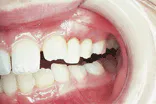

Hand, foot, and mouth disease

The problem: Examination of the head and neck regions revealed enlarged superficial cervical and submandibular lymph nodes.